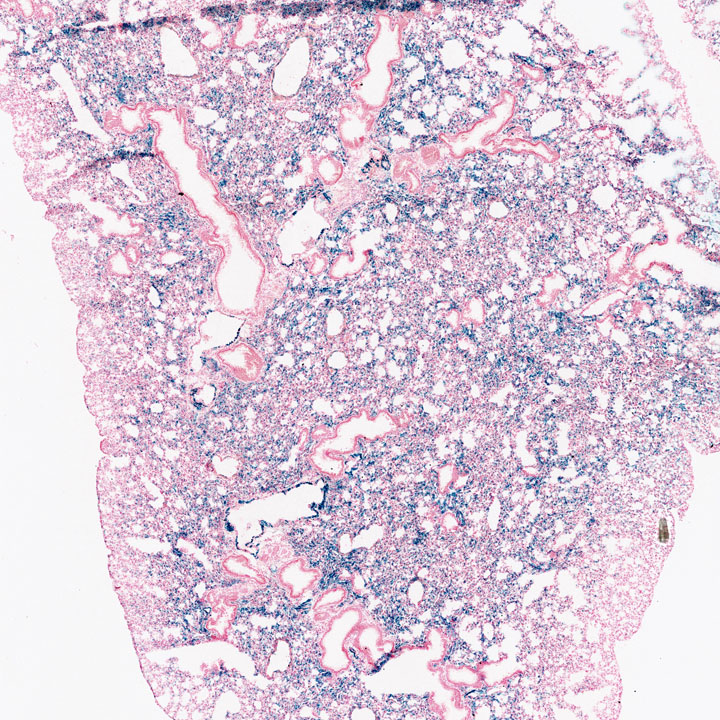

Respiratory System

Images

Drag images to compare to others or to data in the table below. Drag corners to resize images for more detail.

Recombinase Activity